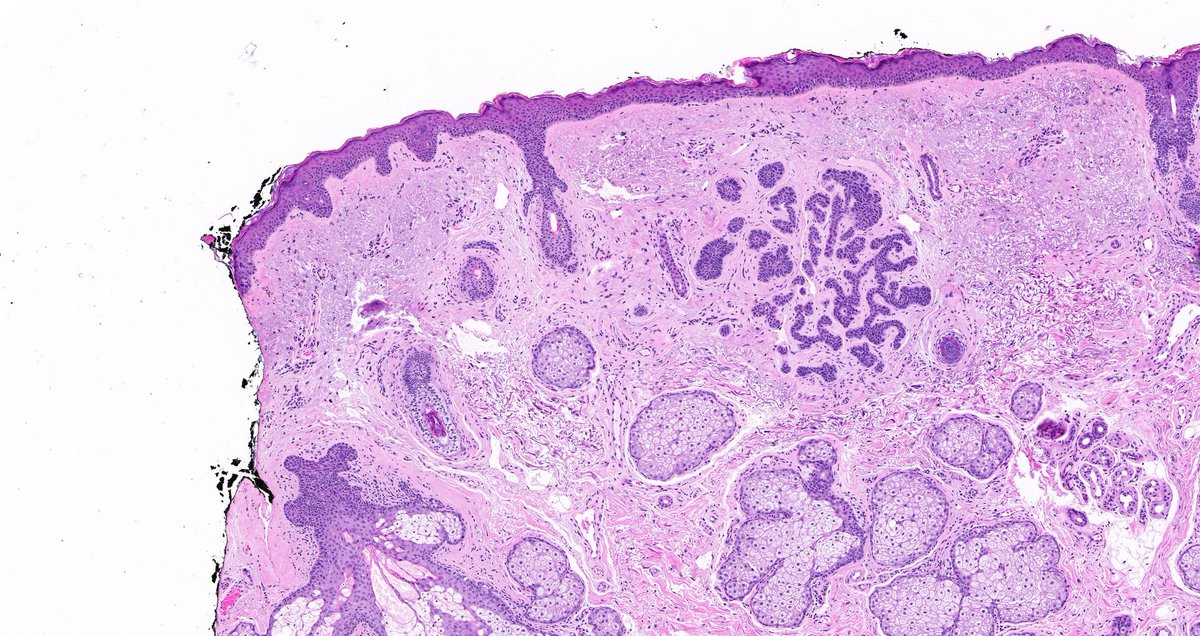

Nasal mucosal mass. Your diagnosis? Answer & more pics here: kikoxp.com/posts/5703. Many thanks to Sadiq M Amer, MD for these incredible images! #pathology #pathologists #pathTwitter #dermpath #dermatology #dermatologia #dermtwitter #ENTpath #microbiology